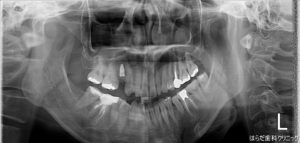

右上5番目の歯茎にインプラントを埋入しました☆